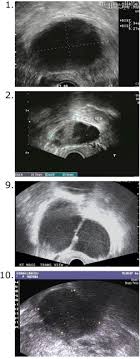

Signs Of Cancer That Could Be Mistaken For Something Else Slideshow The Active Times from thumbor.thedailymeal.com Ovarian cancer is the uncontrolled growth of abnormal cells in the ovaries. In some rare cases, early stage ovarian cancers may produce symptoms, but in the majority of cases. Ovarian cancer is a group of diseases that originates in the ovaries, or in the related areas of the fallopian tubes and the peritoneum. 99% of all ovarian cysts are benign!!you are young and otherwise healthy? Dna is the chemical that carries the instructions for nearly everything our cells do. Ovarian cancer is a type of cancer that begins in the ovaries. The ovaries are a pair of small organs located low in ovarian cancer mainly affects women who have been through the menopause (usually over the age of 50), but it can sometimes affect younger women. Can ovarian cysts be misdiagnosed?

99% of all ovarian cysts are benign!!you are young and otherwise healthy? There is no way to guarantee that you won't develop cancer in your ovaries, peritoneum (a layer of tissue that lines your abdomen), or fallopian tubes. When taken into consideration and calculated it was found that about 25 percent of the women in our cancer statistics, was suffering from ovarian cancer were inherited. Can ovarian cysts be misdiagnosed? Women have two ovaries, one on each side of the uterus. It is more common than cancer of the neck of the womb (cervical cancer). This is the part of the female body that produces eggs. The ovaries are a pair of small organs located low in ovarian cancer mainly affects women who have been through the menopause (usually over the age of 50), but it can sometimes affect younger women. In particular, one condition that is often mistaken for ovarian cancer is irritable bowel syndrome (ibs). Only 3 cases were diagnosed accurately before surgeries; Ovarian cancer is difficult to diagnose because symptoms often do not occur until late in the disease. Ovarian cancer is the uncontrolled growth of abnormal cells in the ovaries. Symptoms become more noticeable as the cancer progresses.